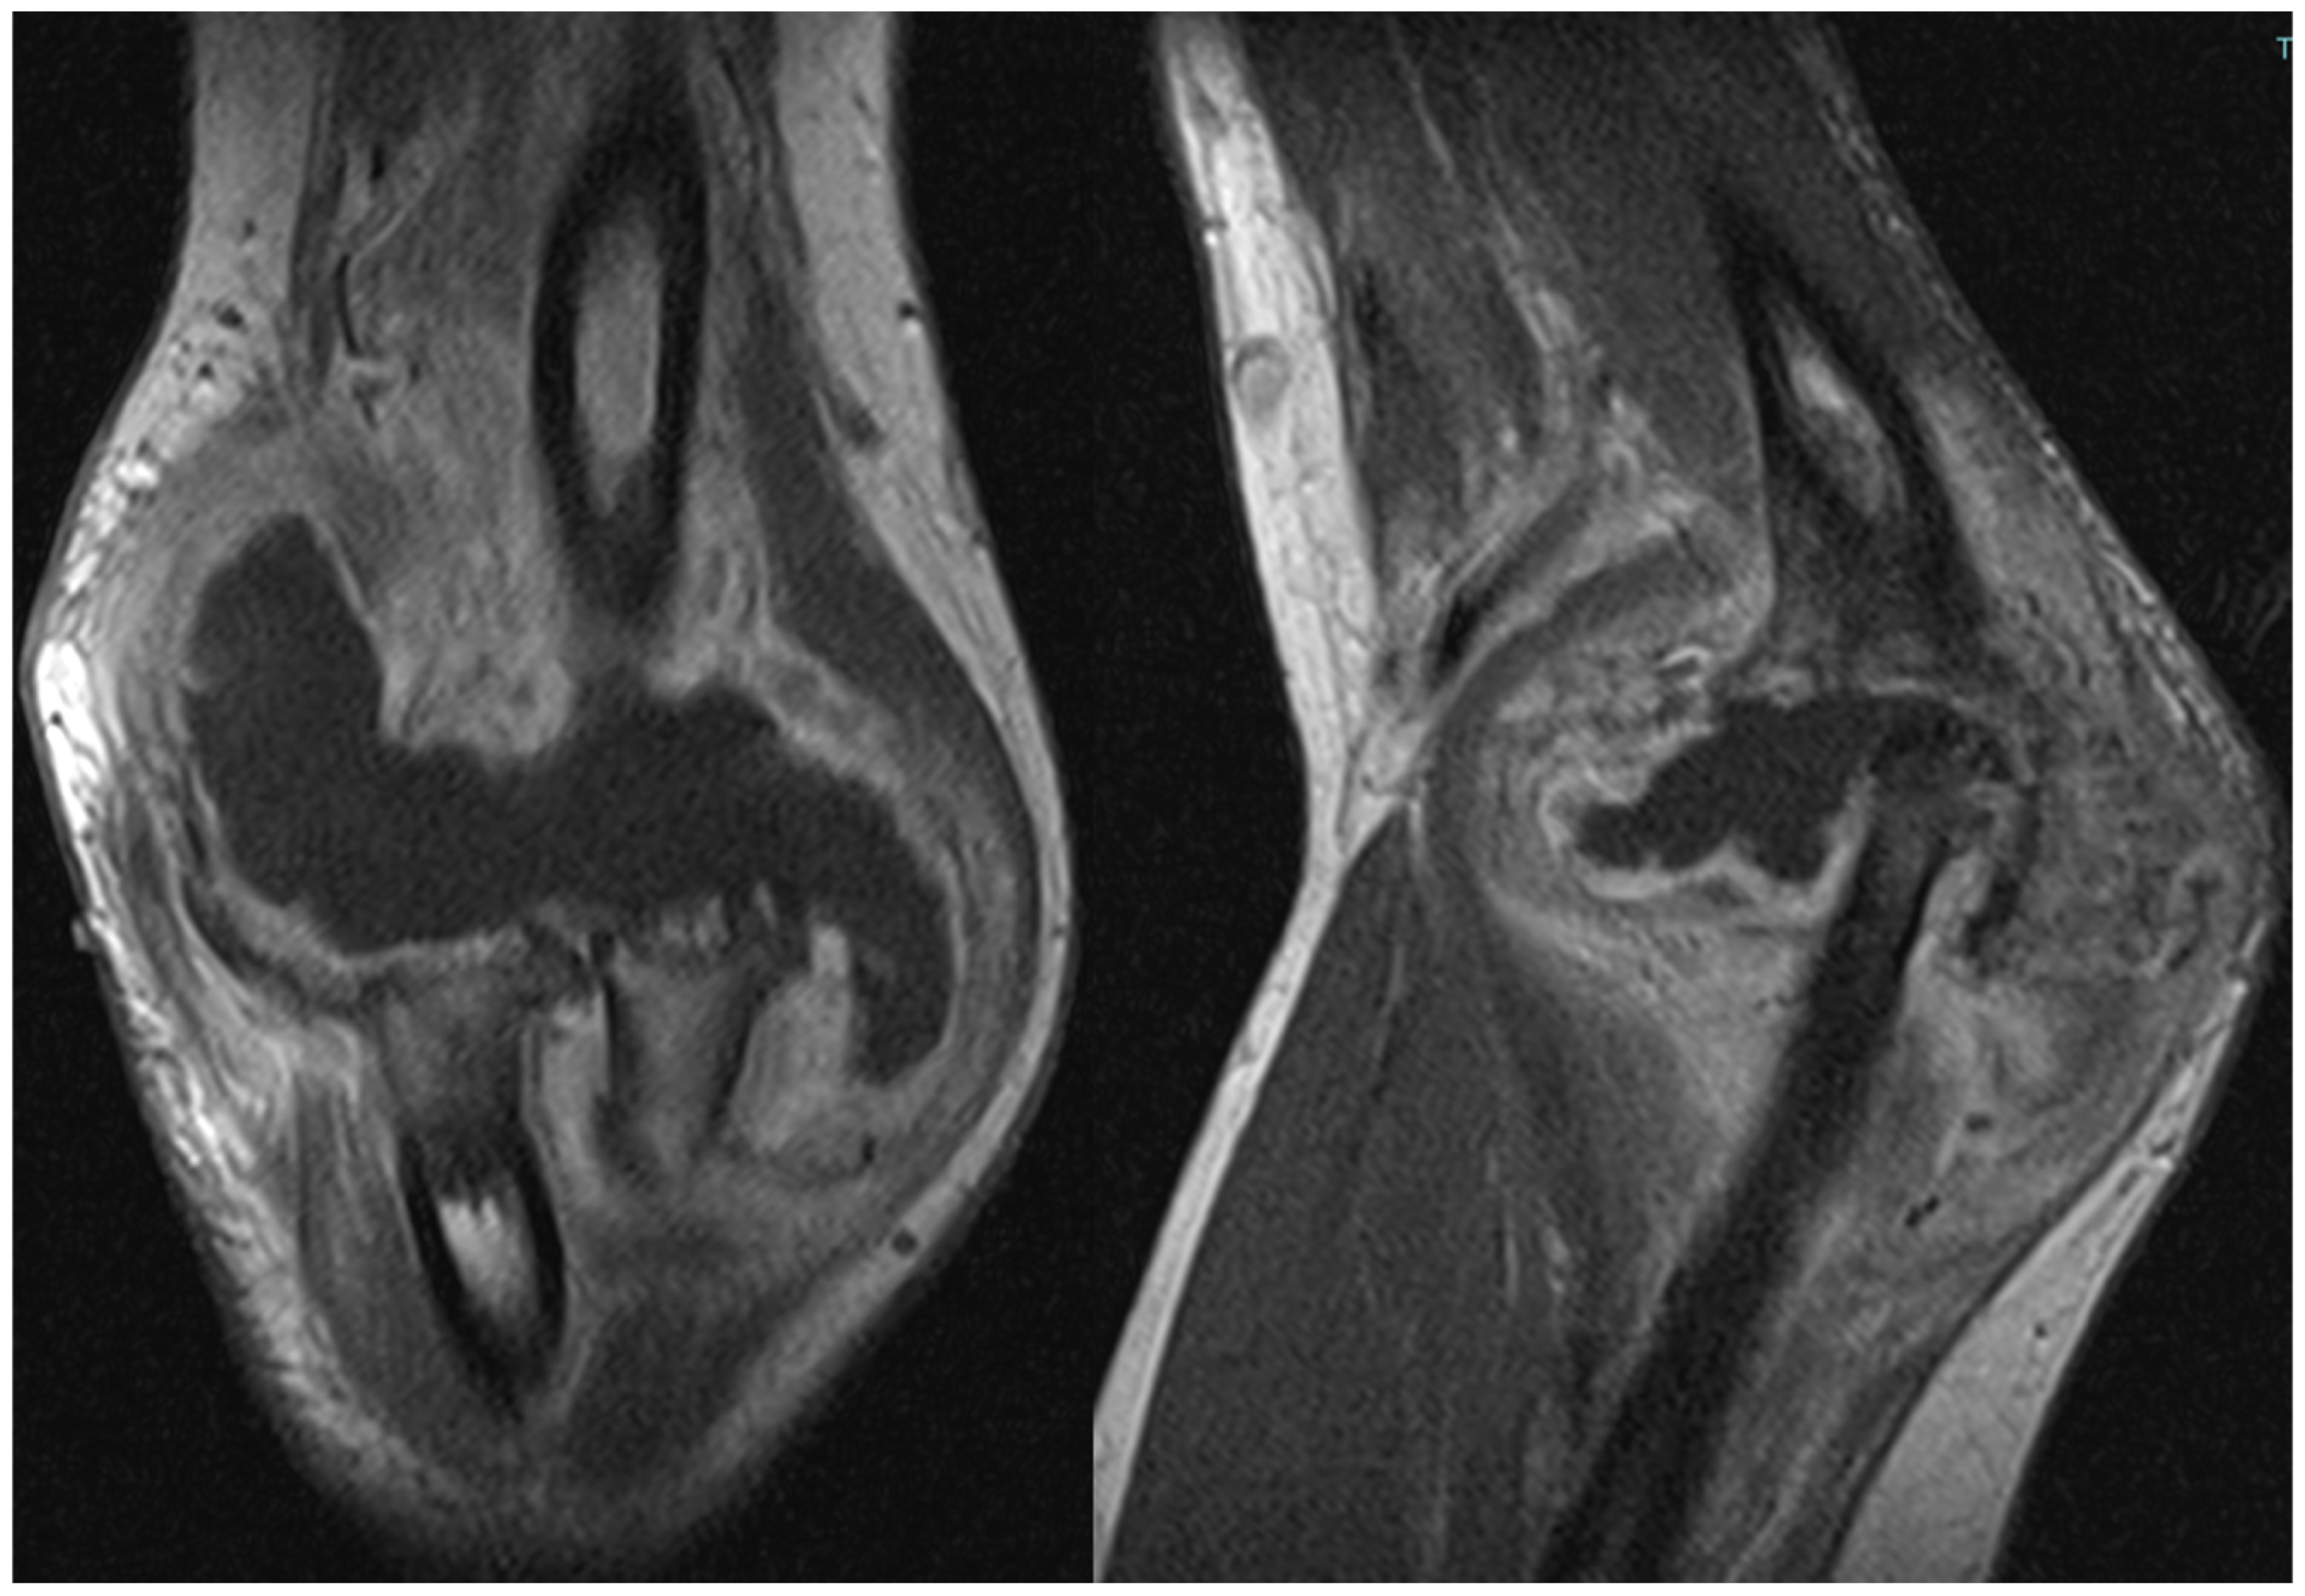

The patient also underwent magnetic resonance imaging (MRI) with and without contrast medium, which demonstrated subluxation between the articular surfaces of the elbow joint, edema and contrast enhancement in the spongy bone of the distal third of the humerus and proximal third of the radius, and a periosteal reaction at the humeral site without identifiable bone lesions, as shown in Figure 3. Additionally, the imaging revealed an abundant layer of joint effusion, with blood clots and loose bodies, at the joint level. The synovium appeared thickened and full of contrast enhancement, and the periarticular soft tissues also displayed thickening with edema and soft contrasting infiltration on the proximal ulnar side. In light of the known basic arthropathy and the patient’s clinical presentation, these radiological findings suggested an arthritic arthro-synovitis picture with soft tissue involvement, without excluding an infectious nature, rather than osteomyelitis, as there was no cavity of necrotic bone with fistula and bone marrow inflammation.

Figure 3.

Magnetic resonance imaging (MRI) coronal and sagittal T1 weight views of the right elbow. Involvement of periarticular soft tissue with a large mass through the articulation.